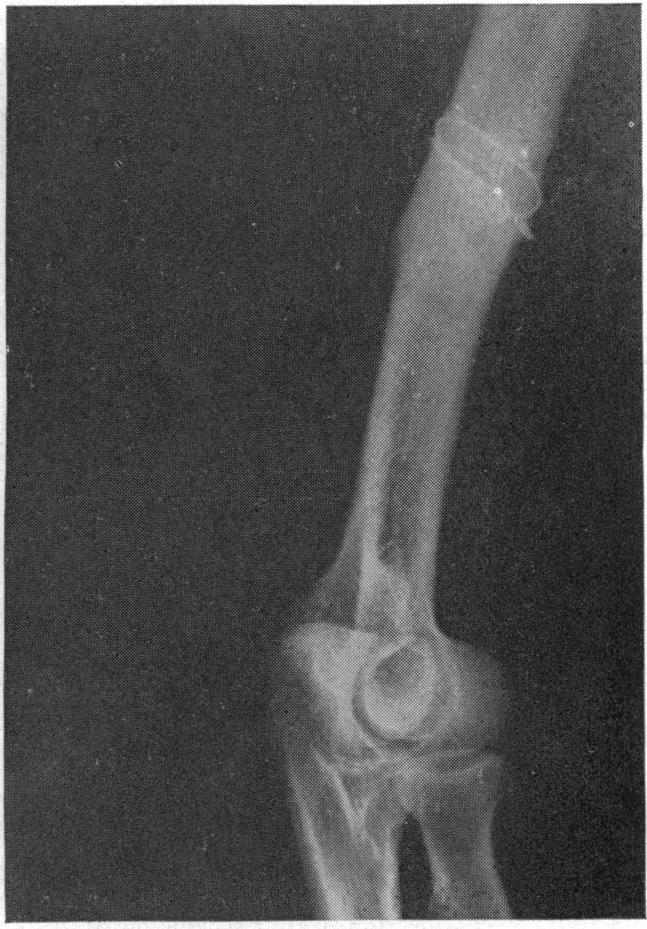

Non-union of fractures of the distal end of the humerus.

J Bone Joint Surg Am. 1988 Jan;70(1):75-83.